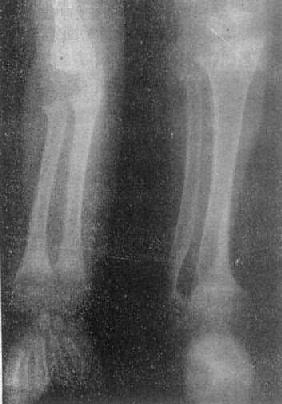

关节退行性变-膝关节退行性骨关节病

图2-1-16 关节退行性变-膝关节退行性骨关节病

膝关节的关节间隙变窄,边角锐利,有骨赘形成,关节面平而致密